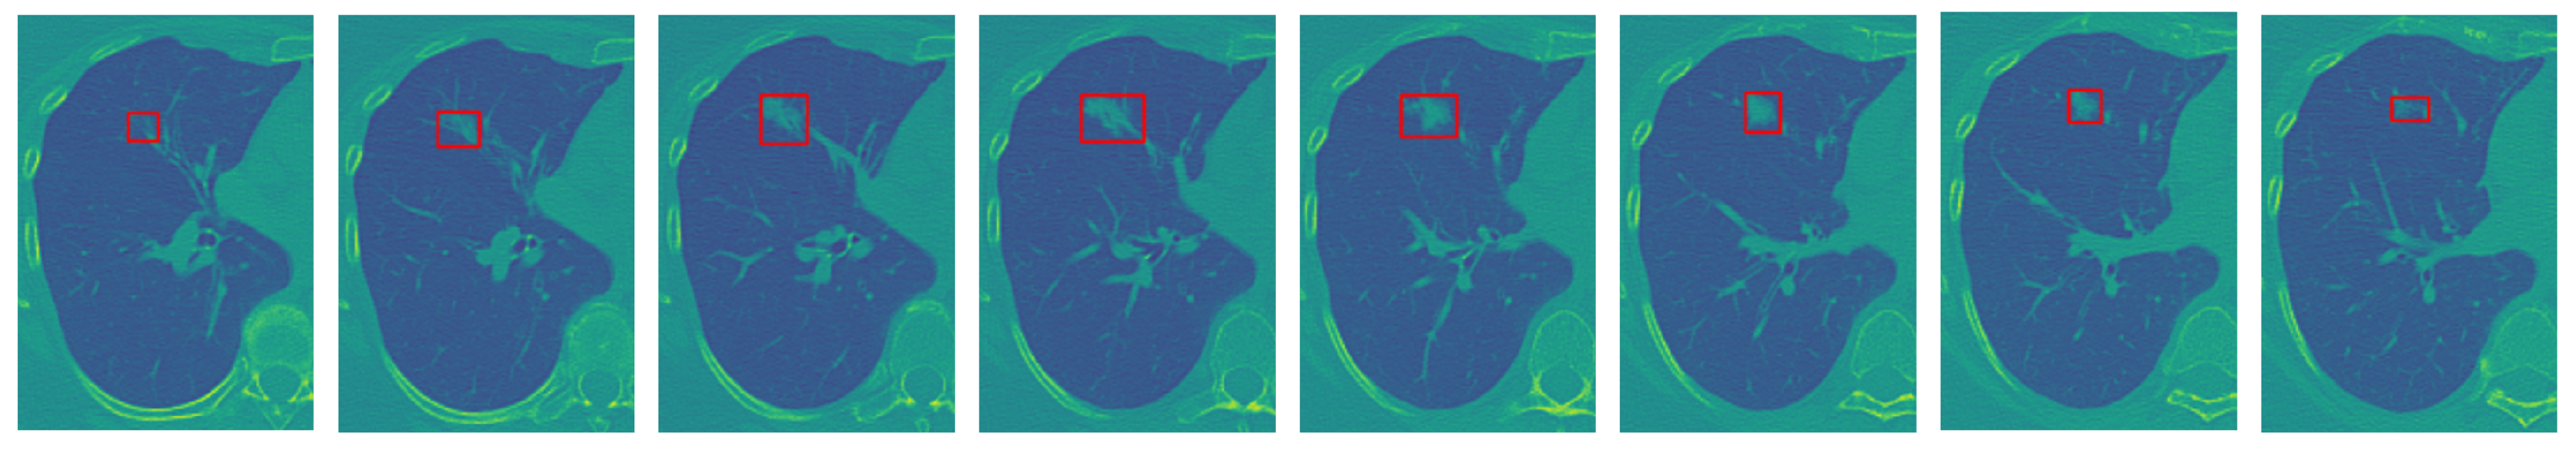

2.3. Deep-Learning Radiomic Features

Figure 4. An illustrative example to clarify the rationale behind integrating temporal and spatial analysis within our framework (the red frame highlights the nodule region of interest): sequence of sample slices in a CT volume of a patient illustrating nodule’s location, size, and shape variation.